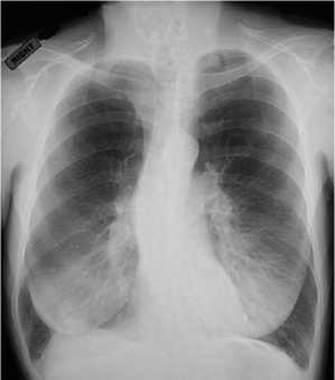

Мал. 105. Емфізема верхніх та середніх відділів легень. Правобічний грудний Сколіоз (рентгенограма).